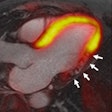

PET/MRI offers details in acute myocardial infarction cases

January 9, 2014